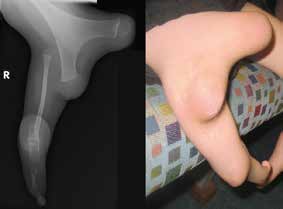

Fibuladefekte mit ausgeprägten Fehlformen und hohen Beinlängendefiziten werden bereits zu Beginn der Versorgung in einer kosmetisch ansprechenden Achsenposition der fehlgebildeten Gliedmaße eingebettet. Die Ausbildung einer Tibia-Antekurvation mit sichtbarem „Dimple“ („Grübchen“, Hauteinziehung) kann bei den hohen Fibuladefekten wie z. B. der Fibulaaplasie häufig beobachtet werden 16 17. Zur Vorbeugung progredienter Entwicklungen sollte die Einbettung des bereits antekurvierten Unterschenkels daher unbedingt eine zirkuläre formschlüssige Vollkontaktbettung mit integrierter Stabilisierung der antekurvierten Tibia aufweisen. Wird dies in der orthoprothetischen Versorgung nicht berücksichtigt, kann sich die Antekurvation im Zuge des Wachstums verstärken.

In Abhängigkeit von der oftmals beobachteten Valgus-Tendenz bzw. ‑Deformität im Kniegelenk muss bei der unterschenkellangen Orthoprothesenkonstruktion auch eine hohe Kondylenbettung der lateralen Femurkondyle in Erwägung gezogen werden. Der noch vorhandene und zumeist minderstrahlige Fuß der fehlgebildeten Gliedmaße sollte in der Konstruktion der Tibia in bestmöglicher achsengerechter Position unterstellt werden. Die kosmetische Gestaltung der Orthoprothese sollte stets die Beinform der kontralateralen Beinseite zum Ziel haben (Abb. 7). Etwaige aufgrund der Formabweichungen bestehende Inkongruenzen der Außenform sollten bei dieser Versorgungsart nicht ausgeglichen werden, da dies zu einem „plumpen“ äußeren Erscheinungsbild führt 18. Auch hier sollten stets konfektionierte normale Schuhe getragen werden können. Liegen abweichende Achsendeformitäten (Valgusfehlstellung) oder Instabilitäten im Kniegelenk (Kreuzbänder) vor, muss an eine begleitende Führung des Oberschenkels gedacht werden.